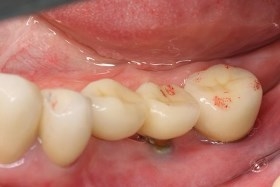

治療前,口內照片;植體外露及牙齦萎縮。

假牙完成,病患恢復健康的角質化牙齦。